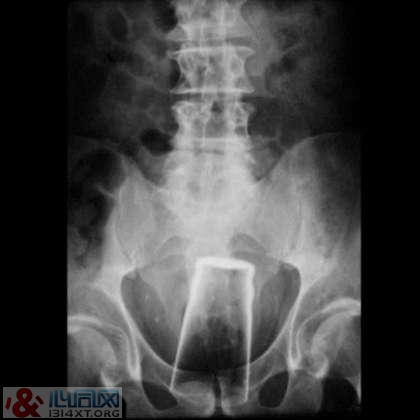

7. 大玻璃杯